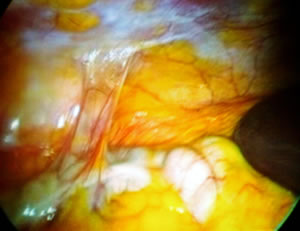

После введения оптики оператор провел ревизию брюшной полости.

На снимке видна печень.

В правой подвздошной области определяется спаечный процесс

от проведенной ранее операции аппендэктомии.

Владимир Леонидович рассек и коагулировал эти спайки кишечника.

На снимке видны участки карбонизации от коагуляции спаек.